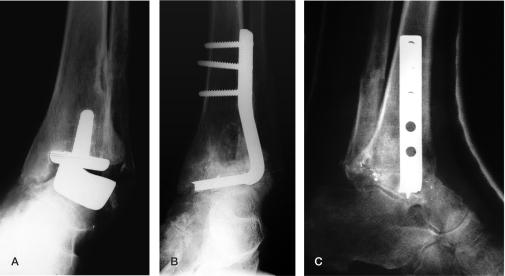

Between 1994 and 2005, salvage arthrodesis was performed on 18 ankles (18 patients). Diagnosis was inflammatory joint disease (IJD) in 15 cases and osteoarthritis (OA) in 3. Tibio-talar fusion was performed in 7 ankles, and tibio-talocalcaneal fusion in 11. Serial radiographs were studied for time to union. Clinical outcome at latest follow-up was measured by the AOFAS score, the foot function index (FFI) and by VAS scores for pain, function, and satisfaction.

Blade plates were used in 7 ankles (4 IJD, 3 OA); all united. Nonunion developed in 7 of the 11 rheumatic ankles stabilized by other methods. 11 patients (8 fused ankles, 3 nonunions) were available for clinical evaluation. Their mean AOFAS score was 62 and mean overall FFI was 70. VAS score for pain was 20, for function 64, and for satisfaction 74. The scores were similar in united and non-united ankles.

Blade plate fixation is successful in salvage arthrodesis for failed TAA. A high nonunion rate was found after salvage ankle arthrodesis in IJD with other methods of fixation. Clinical results were fair to good.